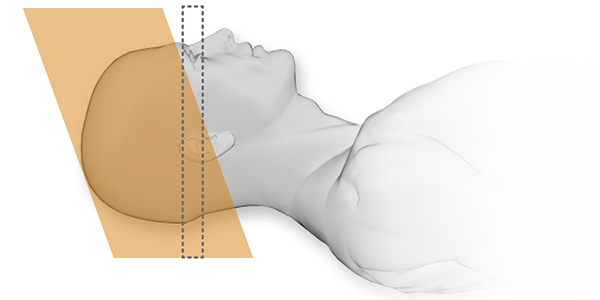

Aquilion Start представляет интуитивно понятную функцию Flex

Технология Organ Effective Modulation (OEM) может дополнять функцию Flex